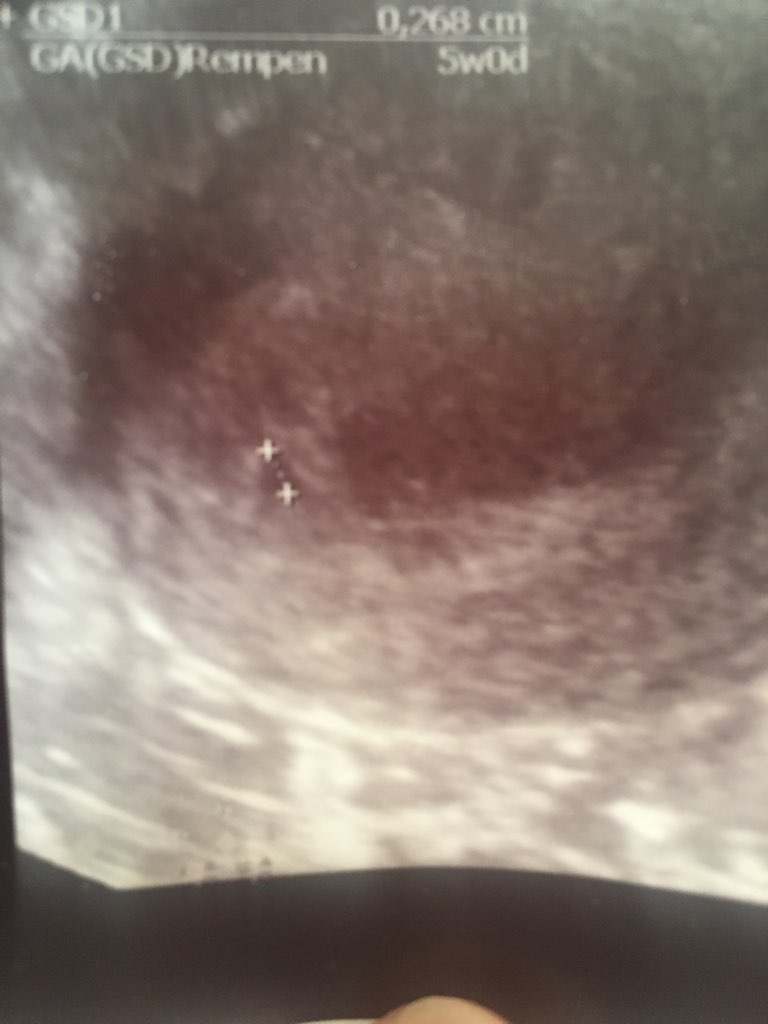

8CB191DA-5602-404A-B5A5-7281B0D6F011.jpg

Moje maleństwo [emoji3060][emoji3060][emoji3060]

Ale Wam zazdroszczę, ze już widzicie! ❤️ Piękne. Dziewczyny a te 5 tygodni liczycie od ostatniej miesiączki?

tak pd ostatniej miesiączki 🙂 teraz zaczęłam się głowić, dlaczego ma tak mało 🥺 nie znam się może to 5dni zrobi taką różnice 🤯 odświeżam temą betę, która miała buc szybko i nie ma 😆